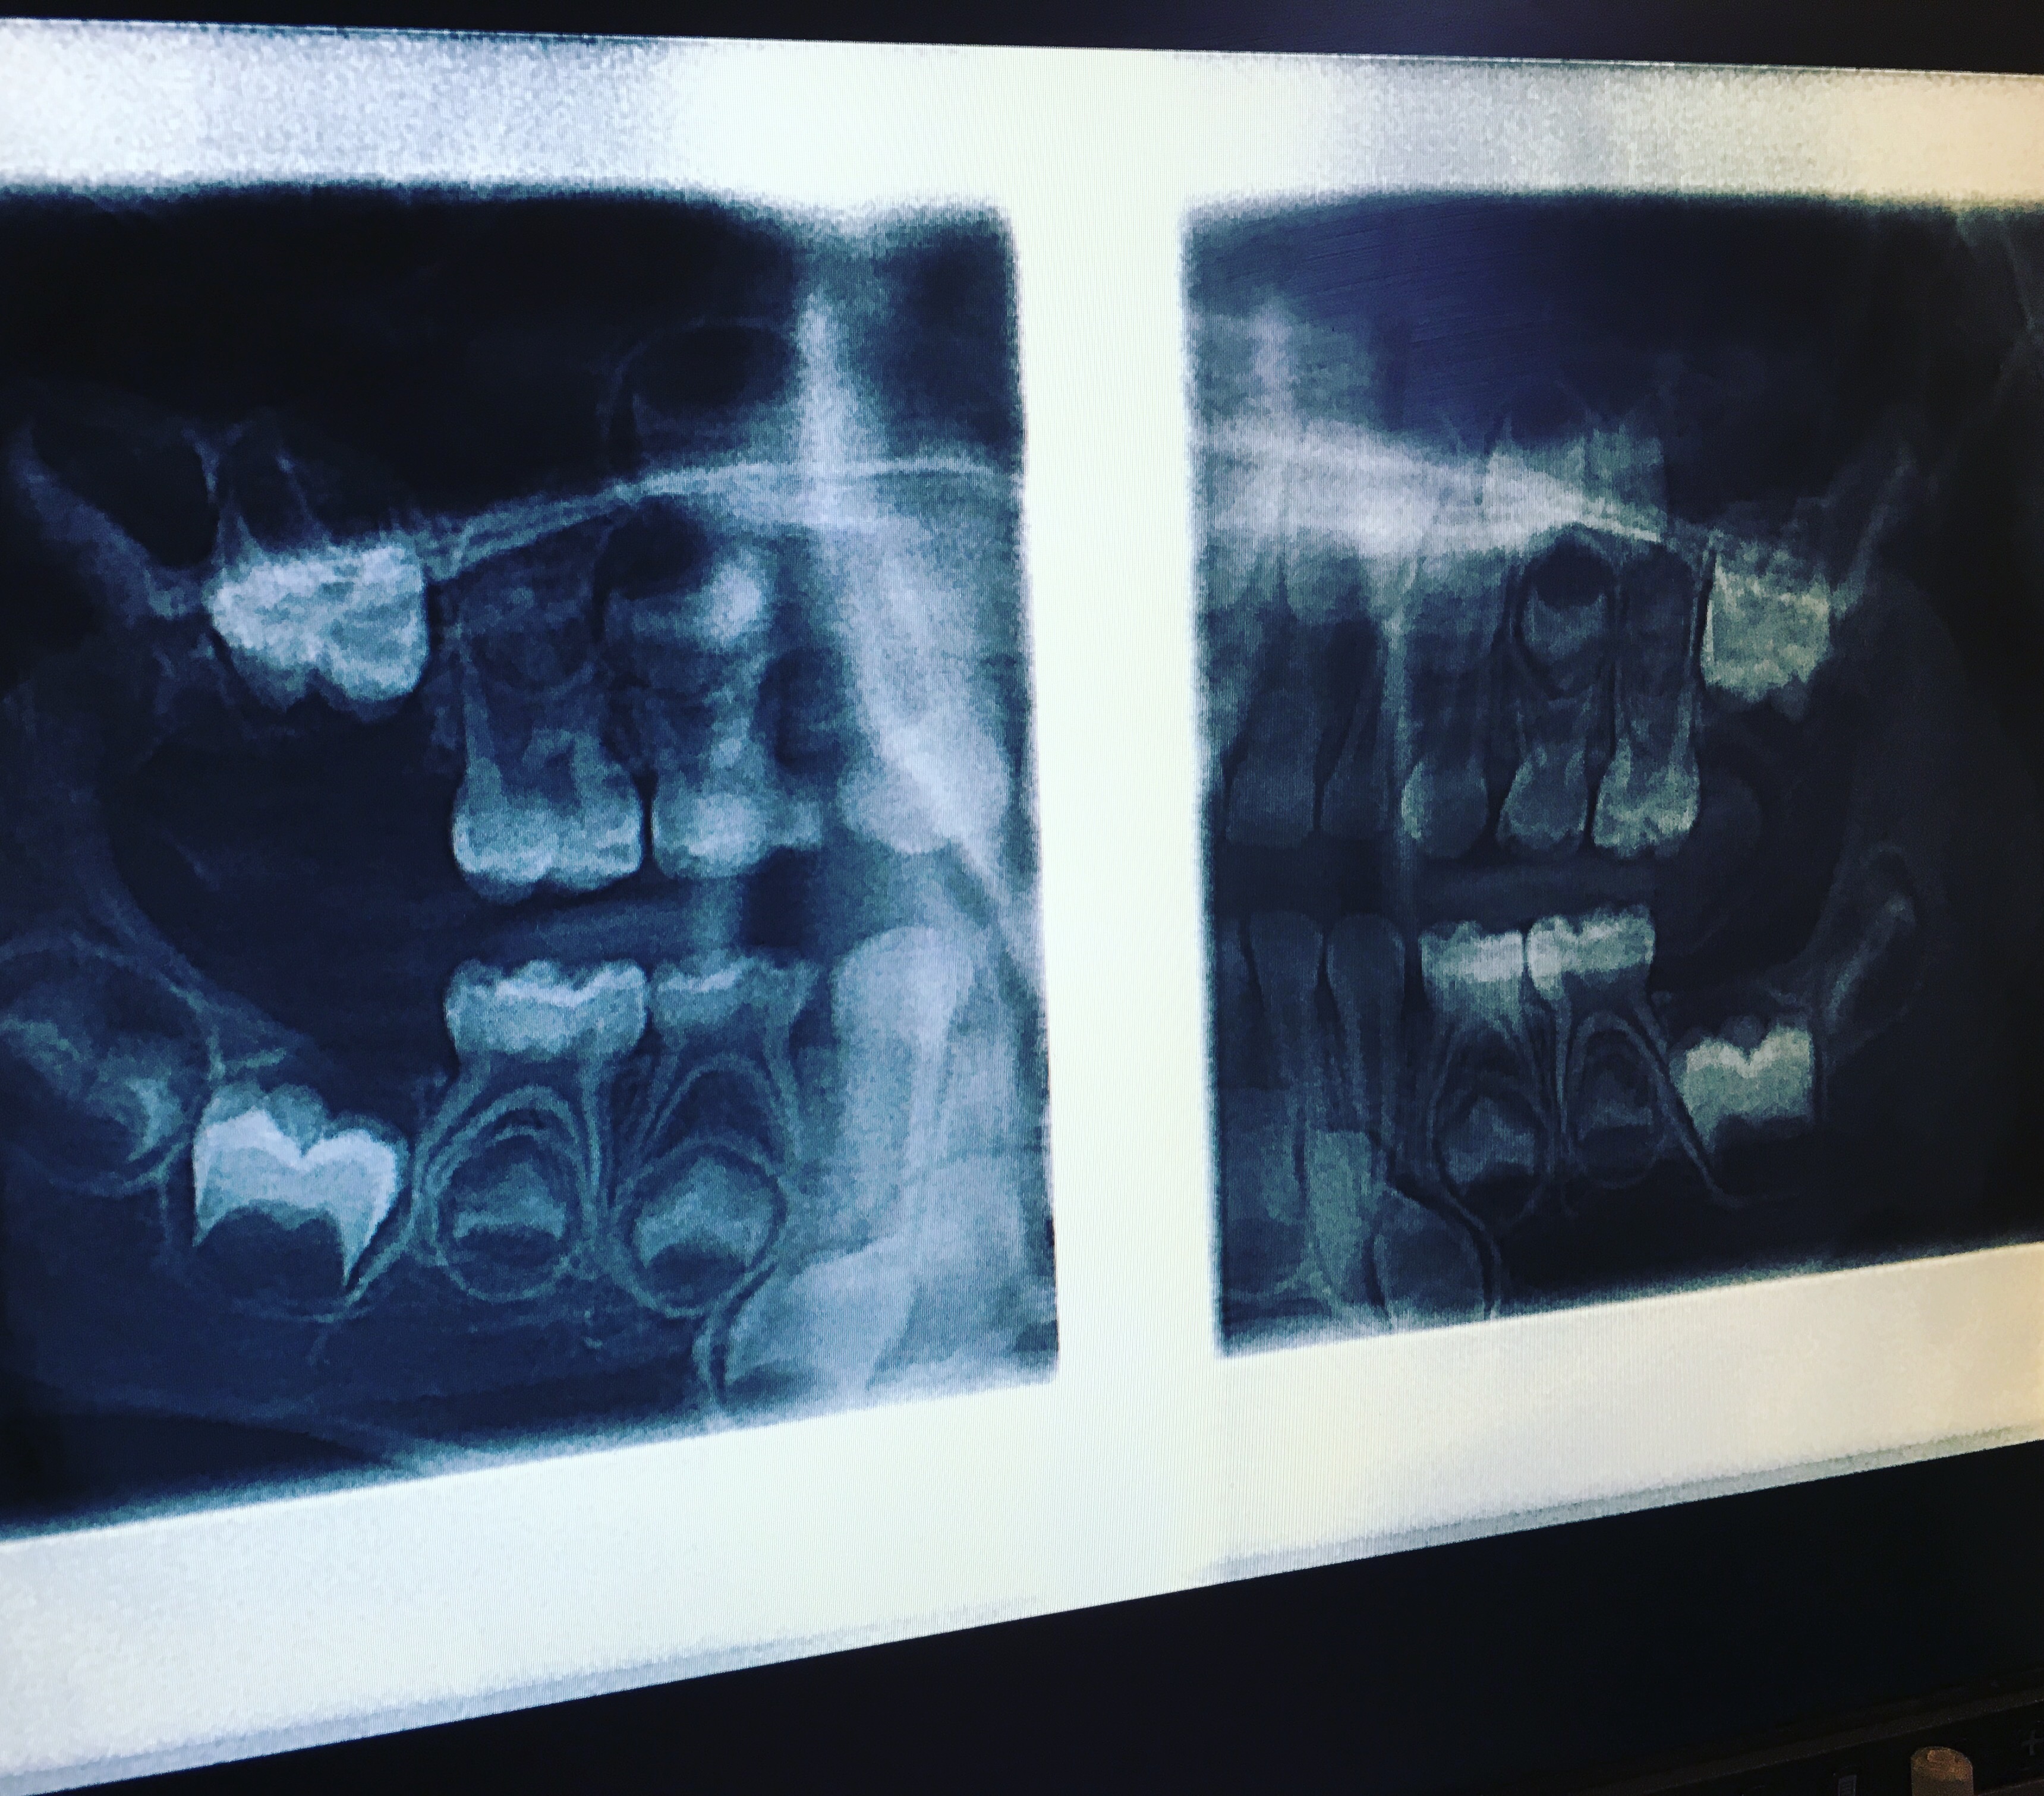

He put up B’s x-rays from his last appointment in October, and said, “Do you have any questions?” And I was like, “Okay, not about this, but so…when do adult teeth form in your face? Like how early?” Drew and I have been debating this, because there’s this picture on the internet of a skull of a child, and it has the baby teeth in the mouth and the adult teeth in the skull above them, and it’s so creepy.

So the dentist said that the adult teeth start forming between ages 1-2, so that means H probably has some adult teeth growing in her face already too, EWWWW. Anyway, below are B’s x-rays, and you can see some of the adult teeth there. Gross.